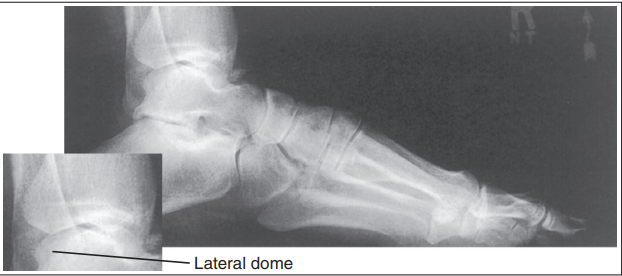

The medial talar dome is demonstrated anterior to the lateral talar dome

Over-rotated/ external rotation

The medial talar dome is demonstrated posterior to the lateral talar dome

Under-rotated/ internal rotation

Medial talar dome is anterior to the lateral dome

Fibula is more posterior

Foot is externally rotated

Medial talor dome is posterior to the lateral dome

Foot is internally rotated